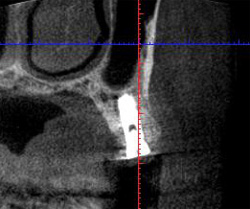

![]() |

3ヵ月後です。骨様組織ができて、インプラントを埋入する骨は十分あります。 |